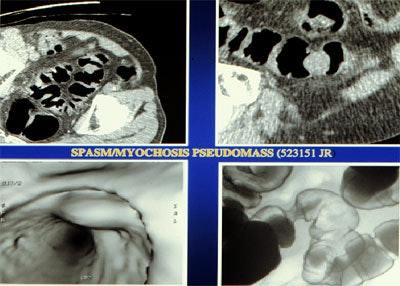

| Top left: prone oblique CT scan of pelvis during virtual colonoscopy showing muscular thickening in sigmoid colon. Top right: multiplanar reformatted image through muscle abnormality (myochosis) simulating a mass. Bottom left: Virtual colonoscopic view of "mass." Bottom right: double-contrast barium enema shows that "mass" is only spasm. Images courtesy of Dr. Marc Gollub. |

The presence of myochosis can make it difficult to distinguish muscular disease from neoplasm, whether in 2-D or 3-D views, he said. For example, if the 3-D view shows a bulging mass in the lumen that can't be identified on CT, sometimes evaluation can be made using double-contrast barium enema "by characterizing the area as a more gradual contraction without proof of any borders, and, more importantly, in the preservation of the mucosa," he said. "This is one of the few times where we think CT shows us too much information and confuses us."

"Myochosis is a morphologic feature of diverticular disease which limits the quality of virtual colonoscopy in the sigmoid colon," Gollub said during his presentation. "Patients with myochosis, with or without diverticula, displayed significantly less sigmoid distension. So we feel that in patients with diverticular disease with myochosis, evaluation of the sigmoid may be limited on VC, and if patients had an incomplete colonoscopy, for example, maybe they should get another test such as the double-contrast barium enema. But VC is still an appropriate examination to look at the remainder of the colon."